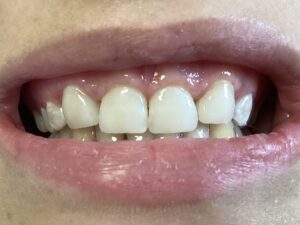

This patient arrived at my practice last week with 2 congenitally missing laterals incisors. Her orthodontist moved the canines into the position of the lateral incisors to fill the gaps but canines don’t look like incisors. They are pointy and “fat” so I told them upfront that although perfect aesthetics will not be achieved we can greatly improve the look and also remove the decay. The procedure required a single 2hr appointment and a very pleasing result was achieved with a very happy teenager leaving the practice that day. Further improvements can be done at a next visit by removing the white spots on the first premolars.